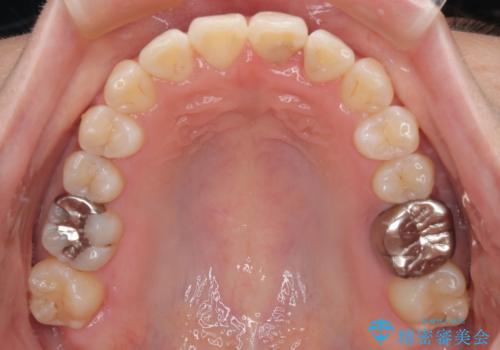

矯正治療期間はわずか10か月と、比較的短期間で終了しました。

前歯のデコボコがなくなり、見た目の印象が大きく変わっただけでなく、歯磨きがしやすくなり、むし歯や歯周病のリスクが大きく減少しました。